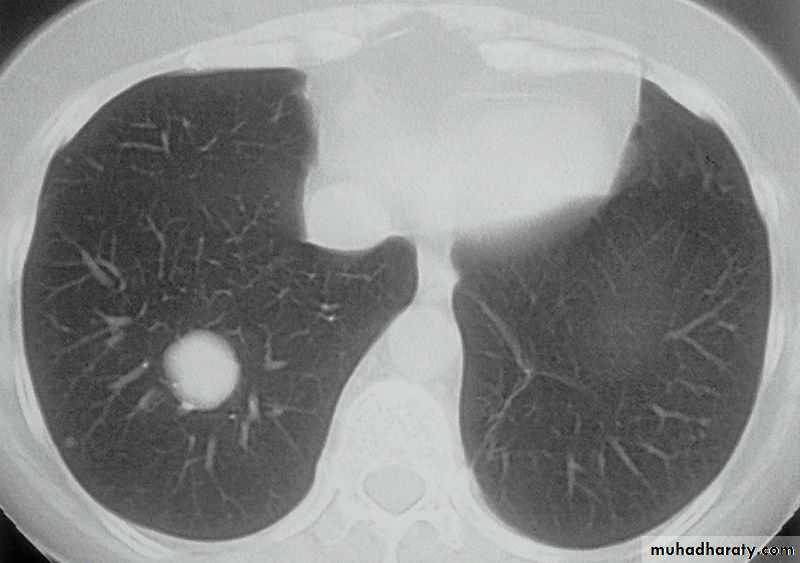

Hydated cyst (simple)

Hydatid cyst (water lily sign)